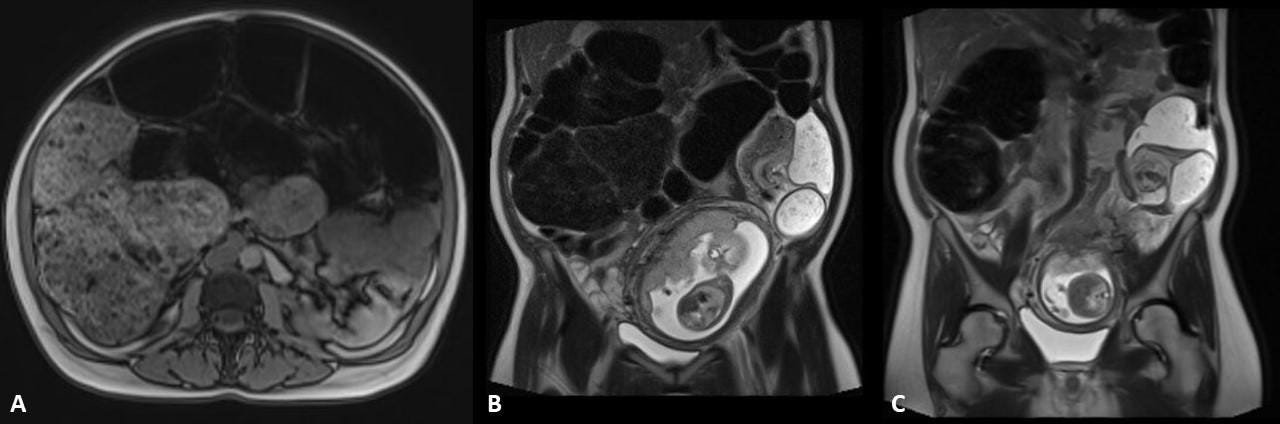

A 40-year-old pregnant woman presented with acute constipation and abdominal distention. A sigmoid volvulus was diagnosed (Figure 1). There was a transition point in the sigmoid colon with a “mesenteric swirl sign” (Figures 1B, 1C).

An emergency colonoscopy was performed to resolve the sigmoid volvulus and place a decompression tube.